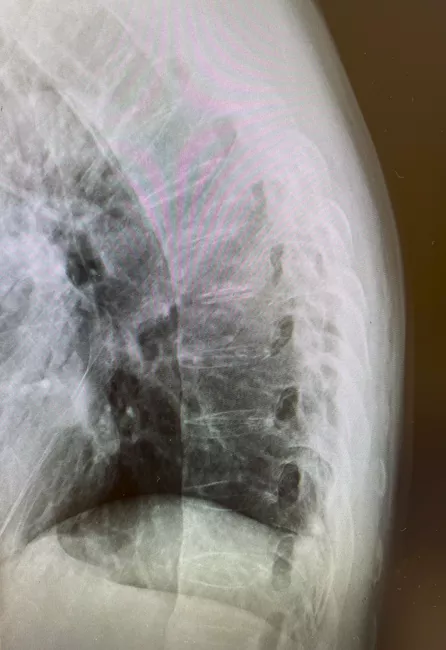

若年男性に発症した、運動により改善して安静により改善しない3か月以上持続する炎症性腰背部痛の所見と血清反応陰性、CRPの上昇より脊椎関節炎を疑った。単純X線では両側仙腸関節に関節裂隙全体の強直を認めgrade4の仙腸関節炎の所見であった(写真1)。また、同写真で腰椎の椎体辺縁に沿った硬化像も認めた(写真1)。追加で行った頸椎(写真2)、胸椎(写真3)、腰椎(写真4)単純X線の側面像では全脊椎の強直(竹様脊椎、bamboo spine)を認めた。以上より強直性脊椎炎と診断した。

写真4 単純X線 腰椎側面像

椎体辺縁に沿った硬化像を認める